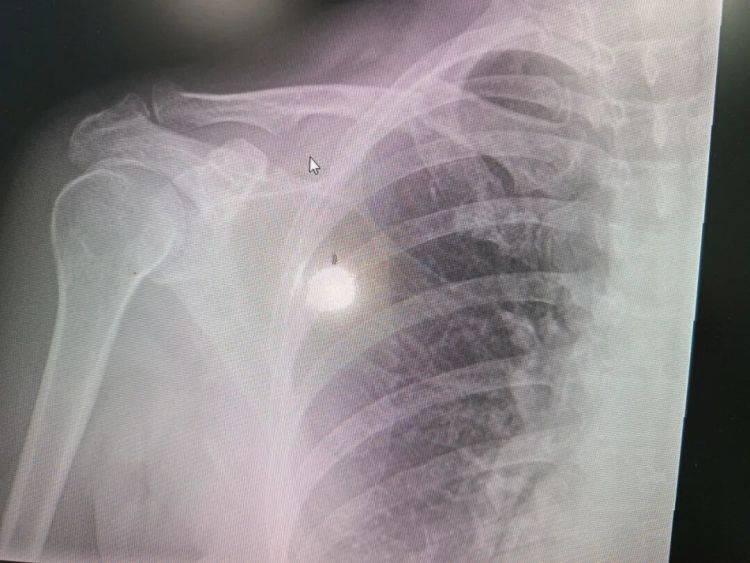

家人赶紧把她送到急诊,X光片显示右侧锁骨骨折。与此同时,血常规结果让人心头一紧:血红蛋白仅有58g/L,属于重度贫血。

“这不是普通的意外骨折,而是病理性骨折。”骨科医生结合贫血指标,当机立断将赵阿姨转入了杭州师范大学附属医院血液内科。

随着病情进展,肿瘤细胞分泌破坏骨骼的因子,导致严重的溶骨性破坏。锁骨作为非承重骨,在轻微外力下发生断裂,说明骨质破坏已经非常严重。